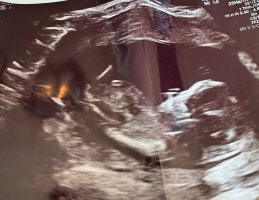

Jeg tipper jente, uten å egentlig ha veldig peilingNoen som vil gjette på disseSynes det er så vanskelig og vite siden begge bildene er så forskjellig, så vet ikke om det ene bildet er nuben som peker sykt opp, eller om det er den lille andre greia under. Chat gtp sa jente på begge, men vet jo at den ikke er til å stole på, så jeg tror kanskje noe annet

GuttNoen som vil gjette på disseSynes det er så vanskelig og vite siden begge bildene er så forskjellig, så vet ikke om det ene bildet er nuben som peker sykt opp, eller om det er den lille andre greia under. Chat gtp sa jente på begge, men vet jo at den ikke er til å stole på, så jeg tror kanskje noe annet

Vis vedlegget 459846